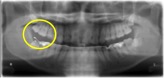

図1 小臼歯の異所萌出

この症例では、犬歯(オレンジ矢印)が生えるべき場所に第一小臼歯(黄色の○)が生えてきています。レントゲンで確認すると、現状ではどうすることもできないため、そのまま経過観察をするという判断になりました。反対側の犬歯(オレンジ矢印)の位置にも問題があります。(図1、2)